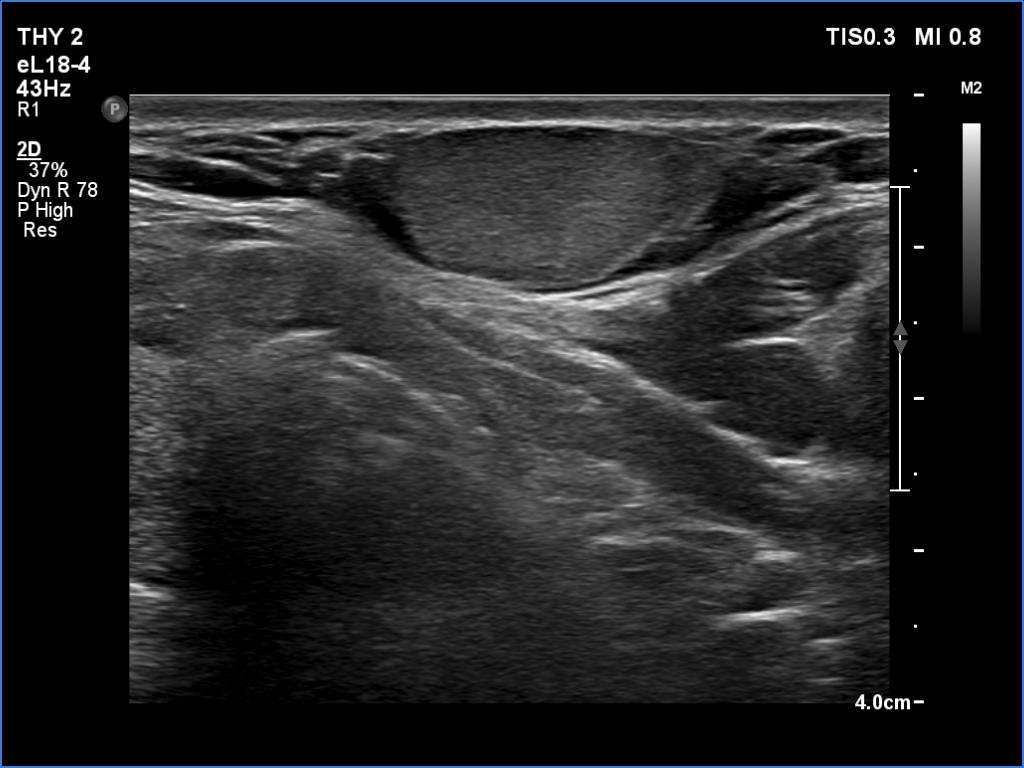

Ultrasonography. The thyroid was echonormal and had several small cystic lesions without any clinical or oncological importance. According to the palpable mass, a moderately hypoechoic lesion was detected several centimeters under the thyroid in the middle of the neck. The lesion was within the muscle tissue. It was homogeneous and presented no vascularity.

Aspiration cytology of the lesion resulted in lipoma.